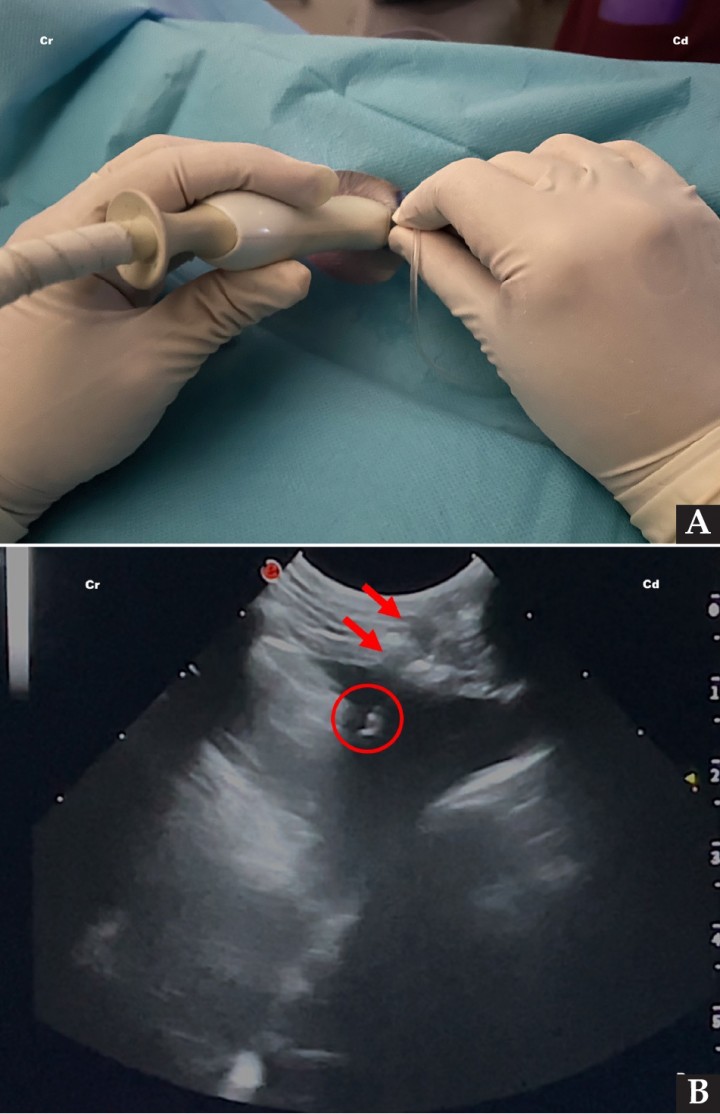

La técnica debe realizarse preferiblemente en decúbito esternal de forma aséptica, tras haber descartado previamente coagulopatías (excepto en pacientes con distrés respiratorio severo, en los cuales se llevará a cabo una toracocentesis de urgencia).[ Lisciandro GR: The abdominal FAST (AFAST) exam. En Lisciandro GR (ed): Focused ultrasound techniques for the small animal practitioner, Oxford, Wiley Blackwell, 2014; 17-43. , Nicolaou S, Talsky A, Khashoggi K, et al.: Ultrasound-guided interventional radiology in critical care. Crit Care Med 2007: 35 (5): S186-S197. [PubMed] ] La sonda ecográfica se debe colocar perpendicular a las costillas (de forma bilateral), generalmente entre el 6º, 7º y 8º espacio intercostal, en el tercio ventral del tórax, y se desplaza craneal y caudalmente hasta encontrar la colección de líquido a la que se desea llegar con la aguja; se debe puncionar siempre craneal a las costillas, minimizando así el riesgo de lacerar los vasos que discurren por el borde caudal de las mismas (Fig. 8).[ Lisciandro GR: The abdominal FAST (AFAST) exam. En Lisciandro GR (ed): Focused ultrasound techniques for the small animal practitioner, Oxford, Wiley Blackwell, 2014; 17-43. , Nicolaou S, Talsky A, Khashoggi K, et al.: Ultrasound-guided interventional radiology in critical care. Crit Care Med 2007: 35 (5): S186-S197. [PubMed] ]

<p>(<strong>A</strong>) Colocación del transductor y de la aguja para la realización de un procedimiento de toracocentesis mediante el acceso caudal, en una técnica estéril para la obtención de líquido pleural. (<strong>B</strong>) Imagen ecográfica del procedimiento de toracocentesis mediante el acceso caudal, en la que se observa el trayecto de la aguja (flechas rojas) y la punta de la misma (círculo rojo) situada en el líquido a extraer. Cr: craneal; Cd: caudal.</p>

(A) Colocación del transductor y de la aguja para la realización de un procedimiento de toracocentesis mediante el acceso caudal, en una técnica estéril para la obtención de líquido pleural. (B) Imagen ecográfica del procedimiento de toracocentesis mediante el acceso caudal, en la que se observa el trayecto de la aguja (flechas rojas) y la punta de la misma (círculo rojo) situada en el líquido a extraer. Cr: craneal; Cd: caudal.